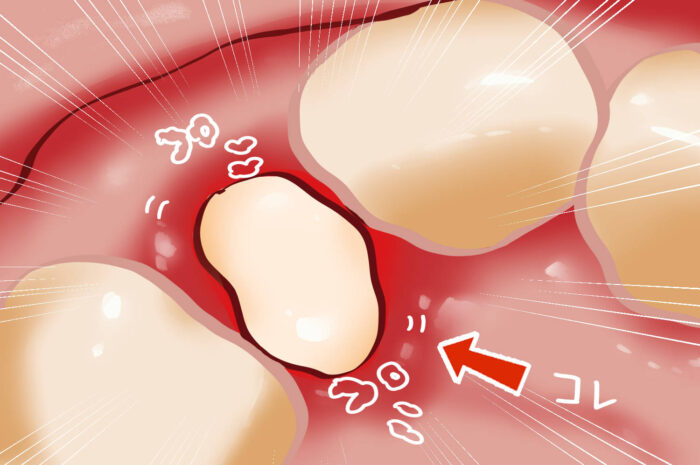

乳歯が抜けたあと乳歯が2本ぬけた写真です。 乳歯は、大人の歯に根っこを食べられて、ぐらぐらになっていきます。 写真の下の歯が先にぬけて何日もたっています。抜けた数日は柔らかい歯茎 肉芽 になっています。 その肉芽が自然に吸収されたり取れたりして、大人の。

乳歯が抜けたあと乳歯が2本ぬけた写真です。 乳歯は、大人の歯に根っこを食べられて、ぐらぐらになっていきます。 写真の下の歯が先にぬけて何日もたっています。抜けた数日は柔らかい歯茎 肉芽 になっています。 その肉芽が自然に吸収されたり取れたりして、大人の。